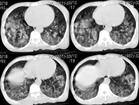

肺臟 肺部的主要病變為出血,以瀰漫性出血最為顯著。是人體對毒力強、數量多的鉤體所引起的全身性強烈反應,有時類似超敏反應。肺瀰漫性出血的原發部位是毛細血管,開始呈少量點狀出血,後逐漸擴大,融合成片或成團塊。組織學檢查可見到肺組織毛細血管完整,但極度充血、淤血以致溢血(並未見到明顯血管破裂現象)。支氣管腔和肺泡充滿紅細胞,部分肺泡內含有氣體,偶見少量漿液滲出。肺水腫極少見。肺出血呈瀰漫性分布,胸膜下多見。超微結構發現大部分肺泡壁毛細血管微結構清晰,可見少量內皮細胞原質呈支狀突起;有的線粒體腫脹,變空及嵴突消失。在變性的內皮細胞內有時可見變性的鉤體;偶見紅細胞從毛細血管內皮細胞間溢出。肺比正常重1~2倍,外觀呈紫黑色。切面呈暗紅色。切開時流出暗紅色或泡沫狀血性液體,氣管或支氣管幾乎全為血液充滿。

⑵肺瀰漫性出血型(肺大出血型):在鉤體侵入人體後,經過潛伏期和短暫的感染早期後的2~3天,突然出現面部蒼白,以後心率和呼吸增快,心慌,煩躁不安,最後進入循環與呼吸功能衰竭。雙肺布滿濕羅音,咯血進行性加劇,但也可無咯血。主要為廣泛的肺臟內部溢血,是近年來無黃疸型鉤體病引起死亡的常見原因。X片顯示雙肺廣泛瀰漫性點片狀軟化陰影。病人在臨終時大量鮮血從口鼻湧出,直至死亡。如能及時套用青黴素和氫化考的松治療,多數患者可獲轉機,3~5天內自覺症狀改善,體徵亦迅速緩解,肺部病灶多在2~4天內可完全消散。據華西醫科大學對本型的研究,認為這是由於機體對病原體及其有毒物質的超敏反應。其理由是:①臨床上來勢猛,恢復也迅速,肺部病灶消失快,沒有血管破裂現象。提示大出血為充血、瘀血和溢血的嚴重後果;②激素治療有特效;③凝血機制正常,沒有DIC現象,不需要抗凝治

①先兆期:患者面色蒼白(個別也可潮紅),心慌,煩躁。呼吸、心率進行性加快,肺部逐漸出現羅音,可有血痰或咯血,X線胸片呈紋理增多,散在點片狀陰影或小片融合。

②出血期:如未及時治療,可在短期內面色轉極度蒼白或青灰,口唇發紺,心慌,煩躁加重,呼吸、心率顯著加快,第一心音減弱或呈奔馬律,雙肺濕羅音逐漸增多,咯血不斷,X線胸片點片狀陰影擴大且大片狀融合。

③垂危期:若未能有效地控制上述症狀,患者可在短期內(1~3小時左右)病情迅速進展,由煩躁不安轉入昏迷。喉有痰鳴,呼吸不整,極度發紺,大口鮮血連續不斷地從口鼻湧出(呈泡沫狀),心率減慢,最後呼吸停止。